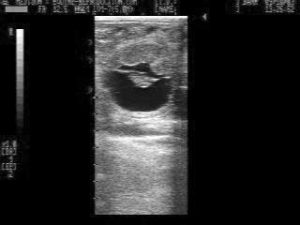

Natural reduction of different sized twin pregnancies seen at days 14, 18 and 33

If the twins are of a different size and touching, one may elect to re-evaluate the pregnancy status no later than day 28 post-ovulation. In the majority of such cases, there is a natural reduction of the pregnancy to a singleton1. For the same reasons listed above, do not hesitate to use prostaglandin at day 28 in the event that you find no apparent reduction, and the presence of two healthy pregnancies!